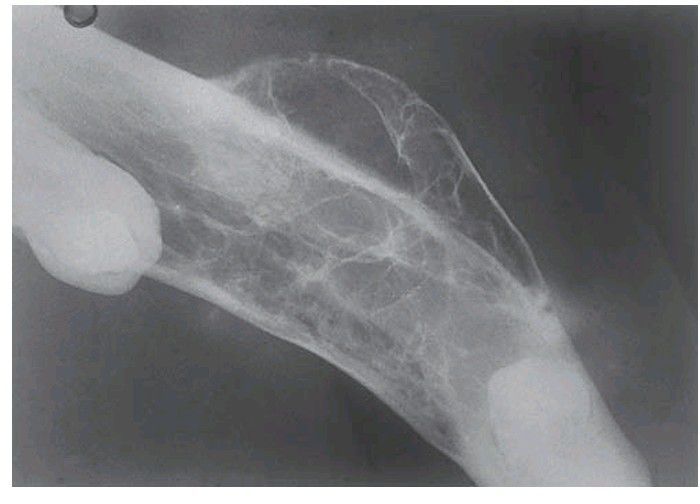

An occlusal view showing the fi nely trabeculated, honeycomb appearance and gross expansion of the mandible. Evidence of residual tumour was still present after 35 years in spite of vigorous treatment, both surgery and radiotherapy, in its earlier stages.